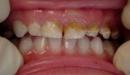

- طبيب الأسنان: تنصح جمعية طب الأسنان الأمريكيّة بزيارة طبيب الأسنان المختص برعاية الأطفال خلال مدّة زمنيّة لا تتجاوز الستة أشهر من لحظة بروز أول أسنان الطفل الرضيع، وذلك ليقوم الطبيب بالتأكد من سلامة نمو الأسنان، كما يقوم الطبيب خلال هذه الزيارة بتقديم بعض النصائح للأم حول الطريقة الصحيحة لرعاية أسنان الأطفال، وبعد الزيارة الأولى للطبيب يمكن تحديد مدّة زمنيّة معيّنة لمراجعته بعدها بشكلٍ دوريّ لمتابعة نمو الأسنان، وتنظيفها لمنع تشكّل التسوّس، ومع تقدّم الطفل بالعُمُر قد يحتاج لتقويم الأسنان في حال كان نموّها غير منتظم.

هناك العديد من الأمراض التي يمكن ان تُصيب الأطفال، منها ما لا يمكن تجنب حدوثه، مثل: التهاب اللوزتين وعدوى الأُذن، وغيرها من المشاكل الصحية الشائعة، ومن الأمراض التي تُصيب الأطفال ما يمكن تجنّبه من خلال حصولهم على المطاعيم بشكلٍ منتظم وتحت إشراف الطبيب المختص، هذا ويجدر بيان أنّ مشاكل الأسنان التي قد يُعاني منها الأطفال بما فيها التسوّس يمكن محاولة تجنّبها من خلال الحرص على سلامة أسنانهم وتنظيفها بشكلٍ مستمر، وتجدرالإشارة إلى وجود بعض المشاكل الصحيّة الناتجة عن بعض التشوهات الخلقيّة المختلفة، مثل تشوهات القلب والتي قد لا تظهر في بداية عُمُر الطفل، والشفة الأرنبيّة (بالإنجليزية: Cleft lip)، وغيرها من الأمراض المختلفة.[٤]